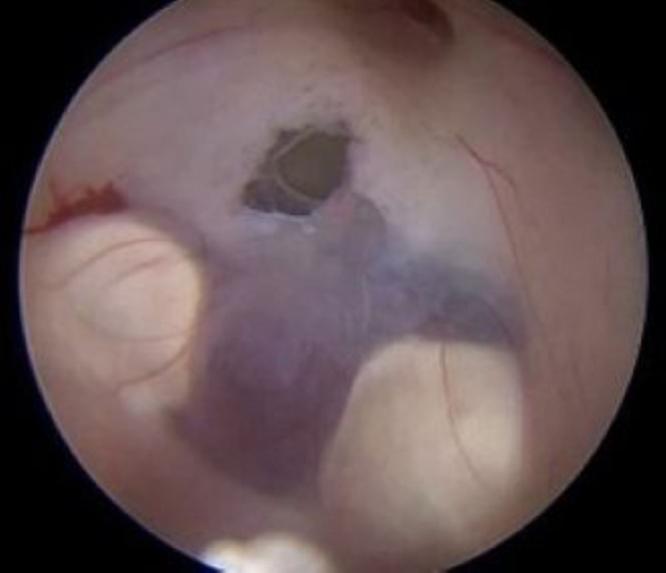

Unreliable sagittal T2-weighted flow void MRI in diagnosing third ventriculostomy: a case of long-standing obstructive hydrocephalus. Illustrative case.

The authors report an illustrative case of pseudo-STV in a 67-year-old man who presented with long-standing obstructive triventricular hydrocephalus. Despite the neuroimaging findings suggesting STV, endoscopic third ventriculostomy showed an intact floor of the third ventricle.

The authors demonstrate the potential for imaging to be misleading in the diagnosis of STV. A flow void artifact on sagittal T2-weighted sequences of the floor of the third ventricle may reflect the fast motion of a thin third ventricular floor or CSF passage through the foramen of Monro rather than flow void through a patent stoma. Endoscopic exploration remains the gold standard for confirming the presence of a ventriculostomy, but other noninvasive tools may help differentiate real CSF intraventricular motion. Dimensional phase-contrast velocity mapping like time-SLIP (arterial spin labeling) MRI could allow the differentiation of flow artifacts caused by the rapid motion of the pulsating floor of the third ventricle from a true ventriculostomy. https://thejns.org/doi/10.3171/CASE2531.